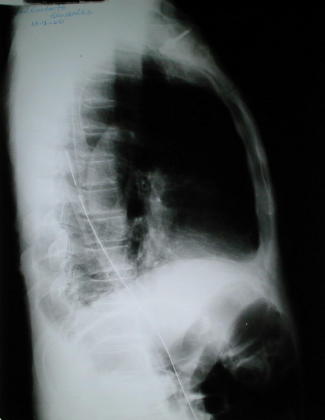

Radiología Pos operatoria

• La radiografía de control pos operatoria inmediato (12 horas), demuestra un diafragma derecho conformado, altura adecuada en relación al diafragma izquierdo, pulmón derecho expandido, escaso líquido pleural residual, asas intestinales distendida por contenido aereo, aguja de cateter venoso subclavio.